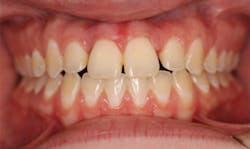

The periodontist surgically exposed the area and, after debridement, noticed an orthodontic rubber band encapsulated with fibrous tissue at the alveolar crest of Nos. 8 and 9 (figure 4). The band was then removed (figure 5) and the area was grafted.

The patient was referred to an orthodontist and, after a comprehensive orthodontic examination, a treatment plan was generated (figure 6). After conventional orthodontic therapy was rendered, the patient was happy with her esthetics, occlusion, and function (figure 7). The patient vowed never again to perform dentistry on herself.